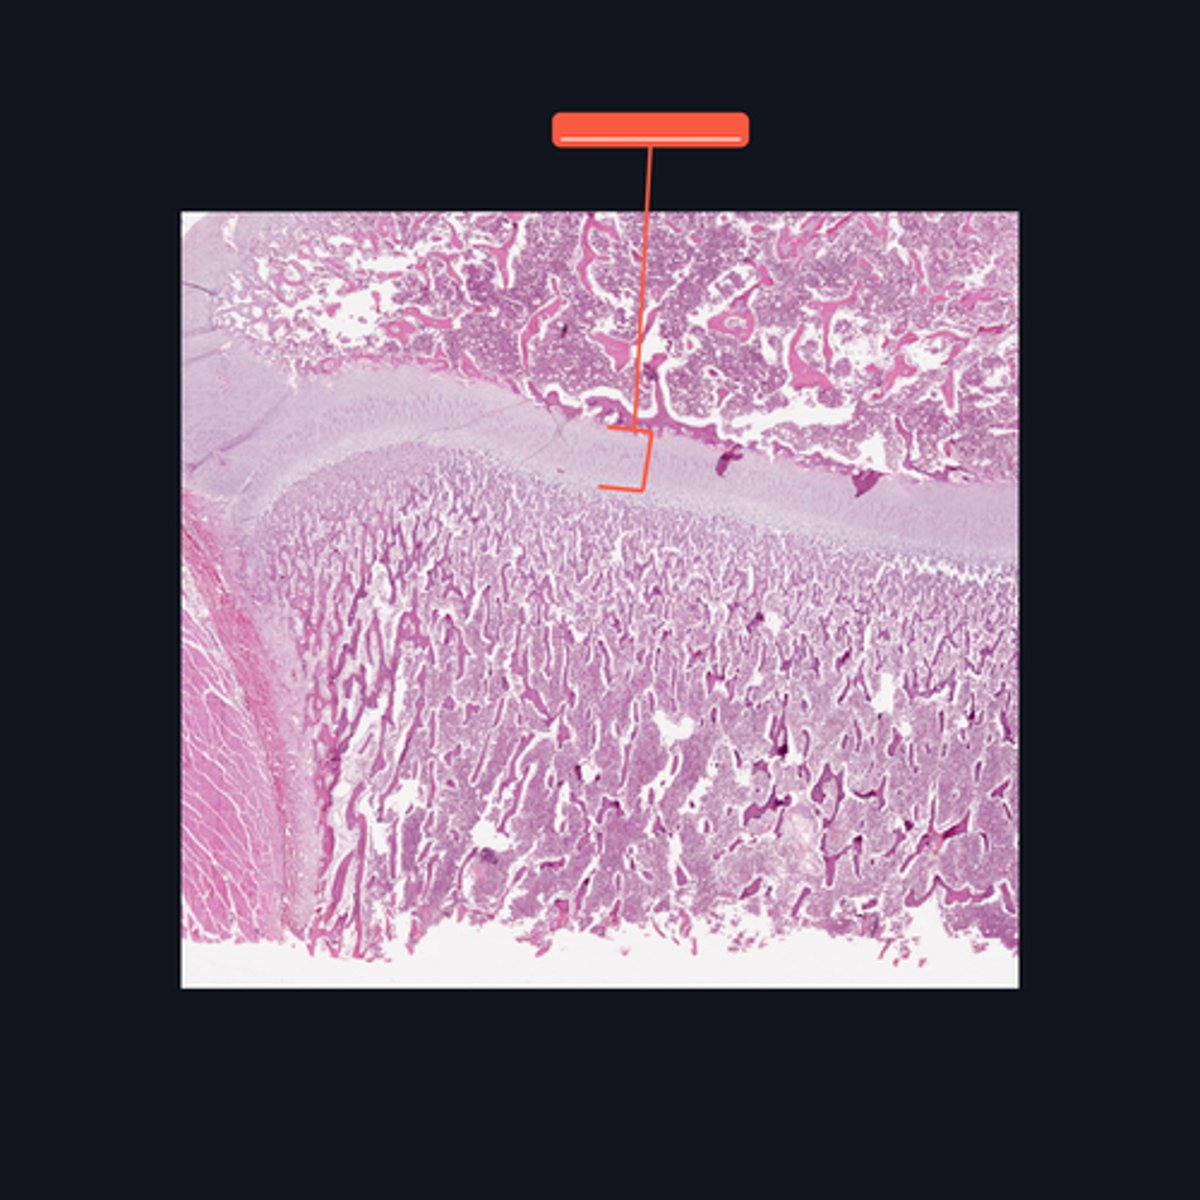

Identify what part of a typical long bone is encompassed by the bracket symbol. It is also known as the _____ of a long bone.

Medullary cavity

Identify the area encompassed by the bracket symbol, which is a hollow core that contains the developing blood cells and spongy bone spicules.

Proximal epiphysis; hyaline cartilage

Identify what part of a typical long bone is encompassed by the bracket symbol. What type of cartilage is it made up of?